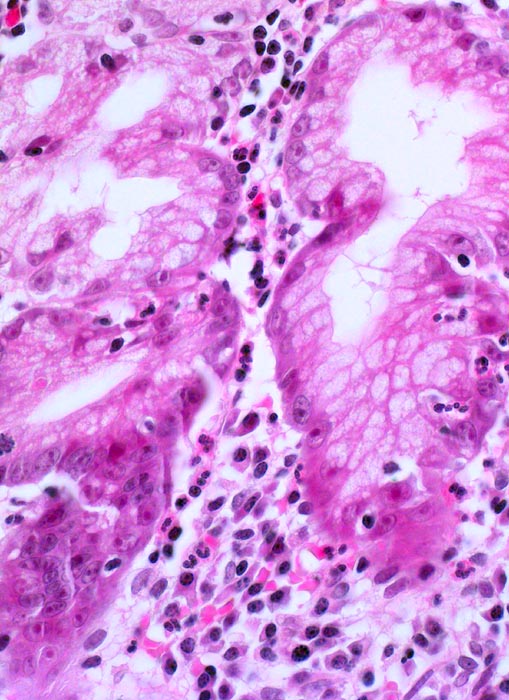

Das Unterrichtspräparat zeigt eine Helicobacter-Gastritis mit intestinaler Metaplasie. Histologisch ist die Typ B Gastritis charakterisiert durch eine chronische (Plasmazellen und Lymphozyten) und aktive (neutrophile Granulozyten) Entzündung. Das Ausmass der chronischen Entzündung und die Entzündungsaktivität werden gemäss Sydney Klassifikation in drei Schweregrade unterteilt (z.B. mässiggradige chronische, stark aktive Gastritis). Fakultativ können Lymphfollikel, eine intestinale Metaplasie mit/ohne Dysplasie und/oder Drüsenatrophie hinzukommen. Die Erreger (Helicobacter pylori) kolonisieren den protektiven Schleimfilm auf der Magenmukosa (> 3330) (> 9968) und sind dort mittels Spezialfärbung (Giemsa C) mikroskopisch nachweisbar. Unmittelbar im Bereich der intestinalen Metaplasie sind aufgrund des veränderten Milieus meist keine Bakterien nachweisbar. Unter Einnahme von Säurehemmern oder Antibiotika verringert sich die Sensitivität des Bakteriennachweises in der Biopsie aufgrund der schnellen Reduktion der Bakterienanzahl ebenfalls. Nach erfolgreicher Eradikation verschwindet in der Regel die aktive Entzündung innert Wochen. Chronische Entzündung und Lymphfollikel bleiben jedoch länger nachweisbar und geben einen Hinweis auf eine abgelaufene Helicobactergastritis.

• Schwere chronische (dichtes lymphoplasmazelluläres Entzündungsinfiltrat in der Lamina propria), stark aktive (neutrophile Granulozyten in der Lamina propria und im Epithel mit Ausbildung von Mikroabszessen) Gastritis.

• An der Schleimhautoberfläche sind einzelne blauviolette kommaförmige Helicobacter Bakterien erkennbar. Die Bakterien sind viel besser in der Spezialfärbung Giemsa C erkennbar (zweiter Präparatlink, ebenfalls Prüfungsstoff!!)

• Intestinale Metaplasie der Antrumschleimhaut: Basophile (bläuliche) Drüsenschläuche mit Becherzellen sowie einzelnen Paneth'schen Körnerzellen mit rot granuliertem Zytoplasma im untersten Schleimhautfragment. Die metaplastische Schleimhaut erinnert stark an Kolonschleimhaut.